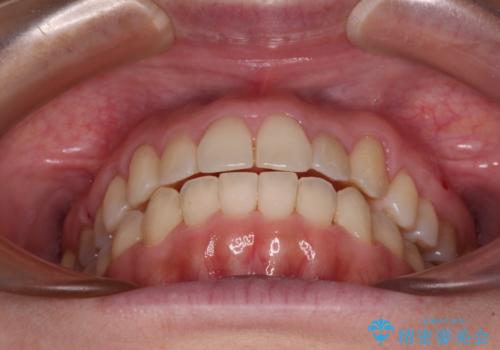

狭い歯列を拡大 拡大装置を併用したインビザライン矯正

インビザラインによる矯正治療を希望されたため、上顎歯列の側方拡大奥歯の遠心移動のための補助装置を併用し、その後はインビザラインにて行うこととしました。

八重歯の動きが鈍く、治療期間は長期化しました。

癒着の疑いもありましたが、アンカースクリューを多用し、何とか改善することができました。